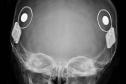

Paraná assume liderança nacional em implantes cocleares pelo SUS

Foto: SESA